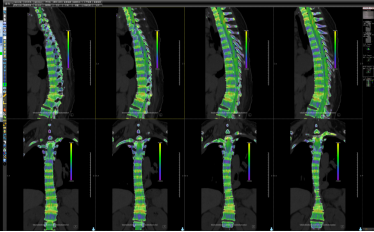

图⑥ 双源CT不同能级下扫描虚拟去钙技术对于骨髓水肿的判定。

图⑦ 双源CT不同能级下扫描后重建对痛风石检出。